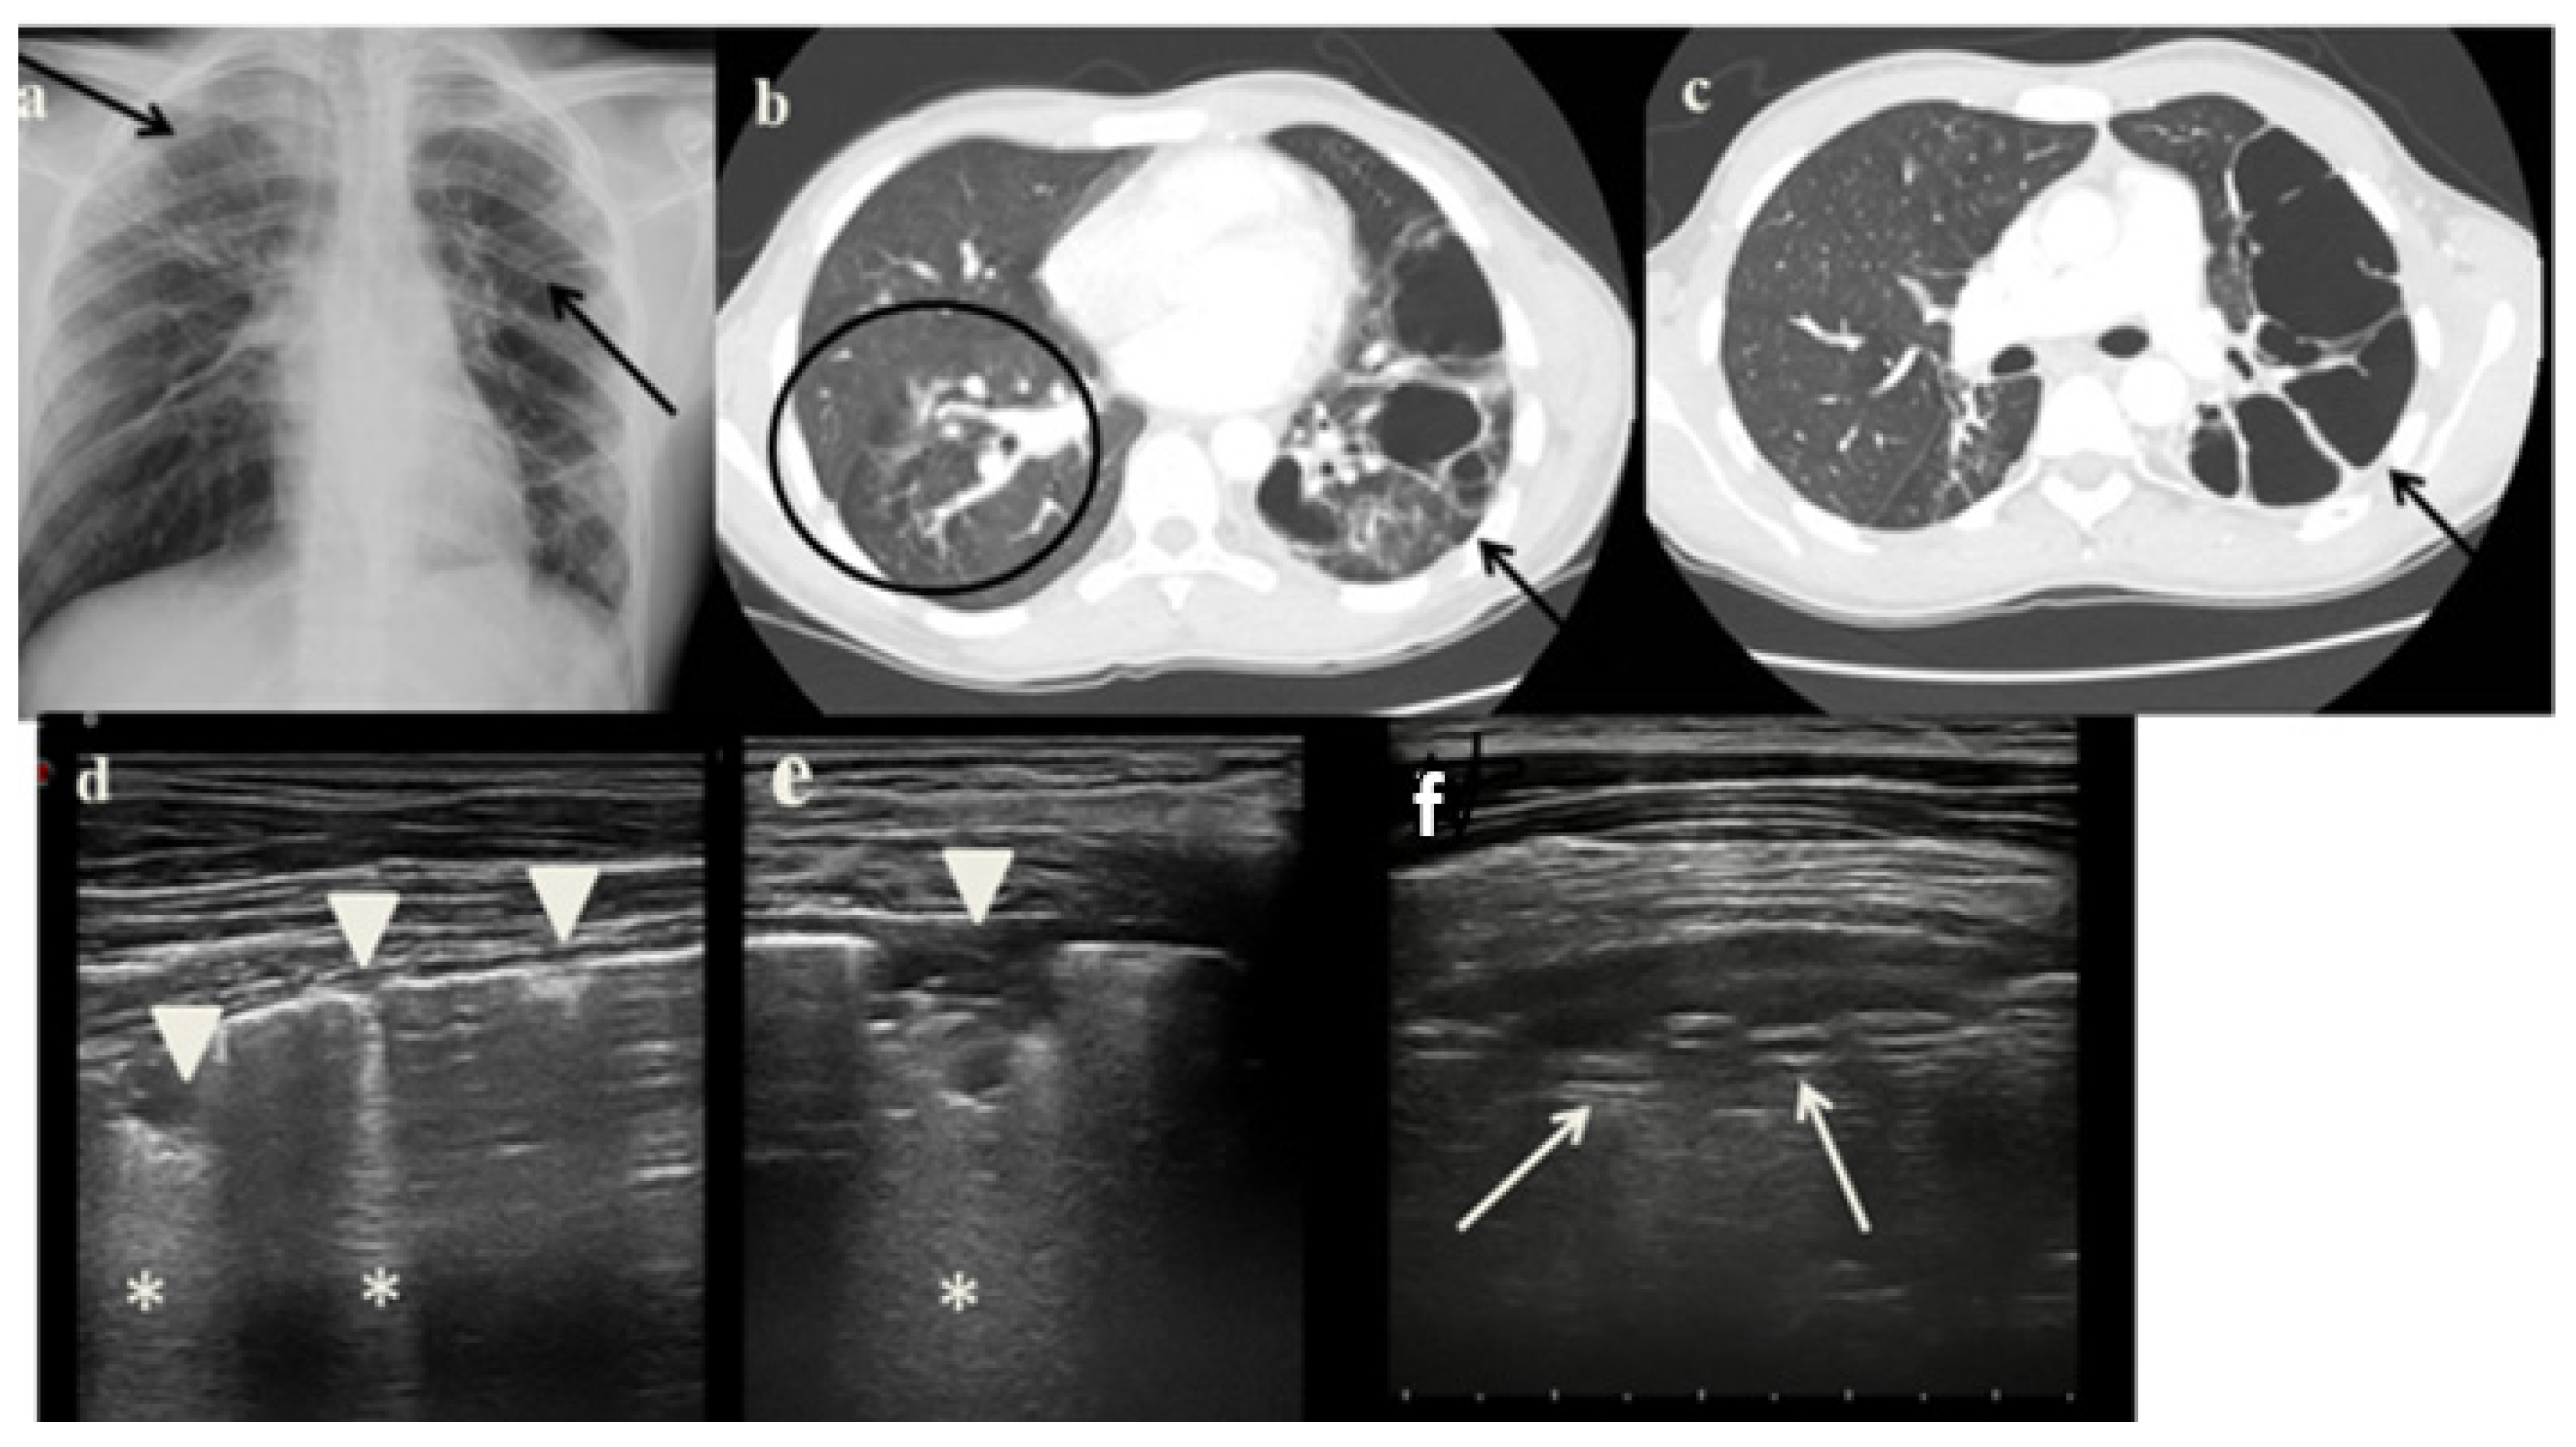

2.3. Case 3

- It identified in cases 1 and 3 large consolidations (Figure 1c and Figure 3c) with significant air content documented by thickened aerial broncograms. We have noticed that the latter have different characteristics compared to the air bronchograms present in bacterial or viral pneumonia [9]. These large consolidations could represent the tubercular cavitation seen at chest CT, but all these findings still need to be studied to better clarify their meaning;